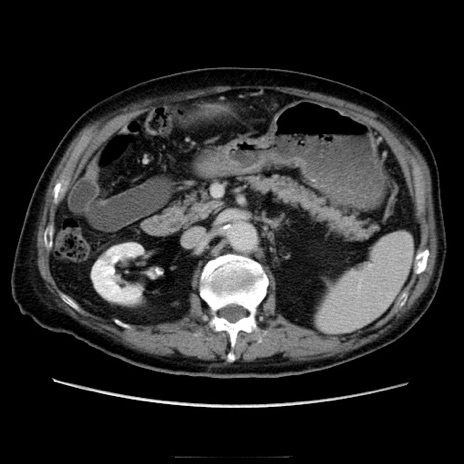

症例21(横断像)

【症例】70歳代男性

【主訴】腹痛

【現病歴】肝硬変・肝細胞癌にてかかりつけの方。約9時間前に食後より腹痛出現。症状が徐々に増悪し、嘔吐出現したため来院。

【既往歴】肝硬変、肝細胞癌(RFA、TACE後)

【身体所見】意識清明、表情苦悶様、BT 36℃、BP 129/78mmHg、P 88bpm、SpO2 97%(RA)、右上腹部から心窩部にかけて圧痛あり、反跳痛なし、筋性防御あり。

【データ】WBC 5800、CRP 0.16